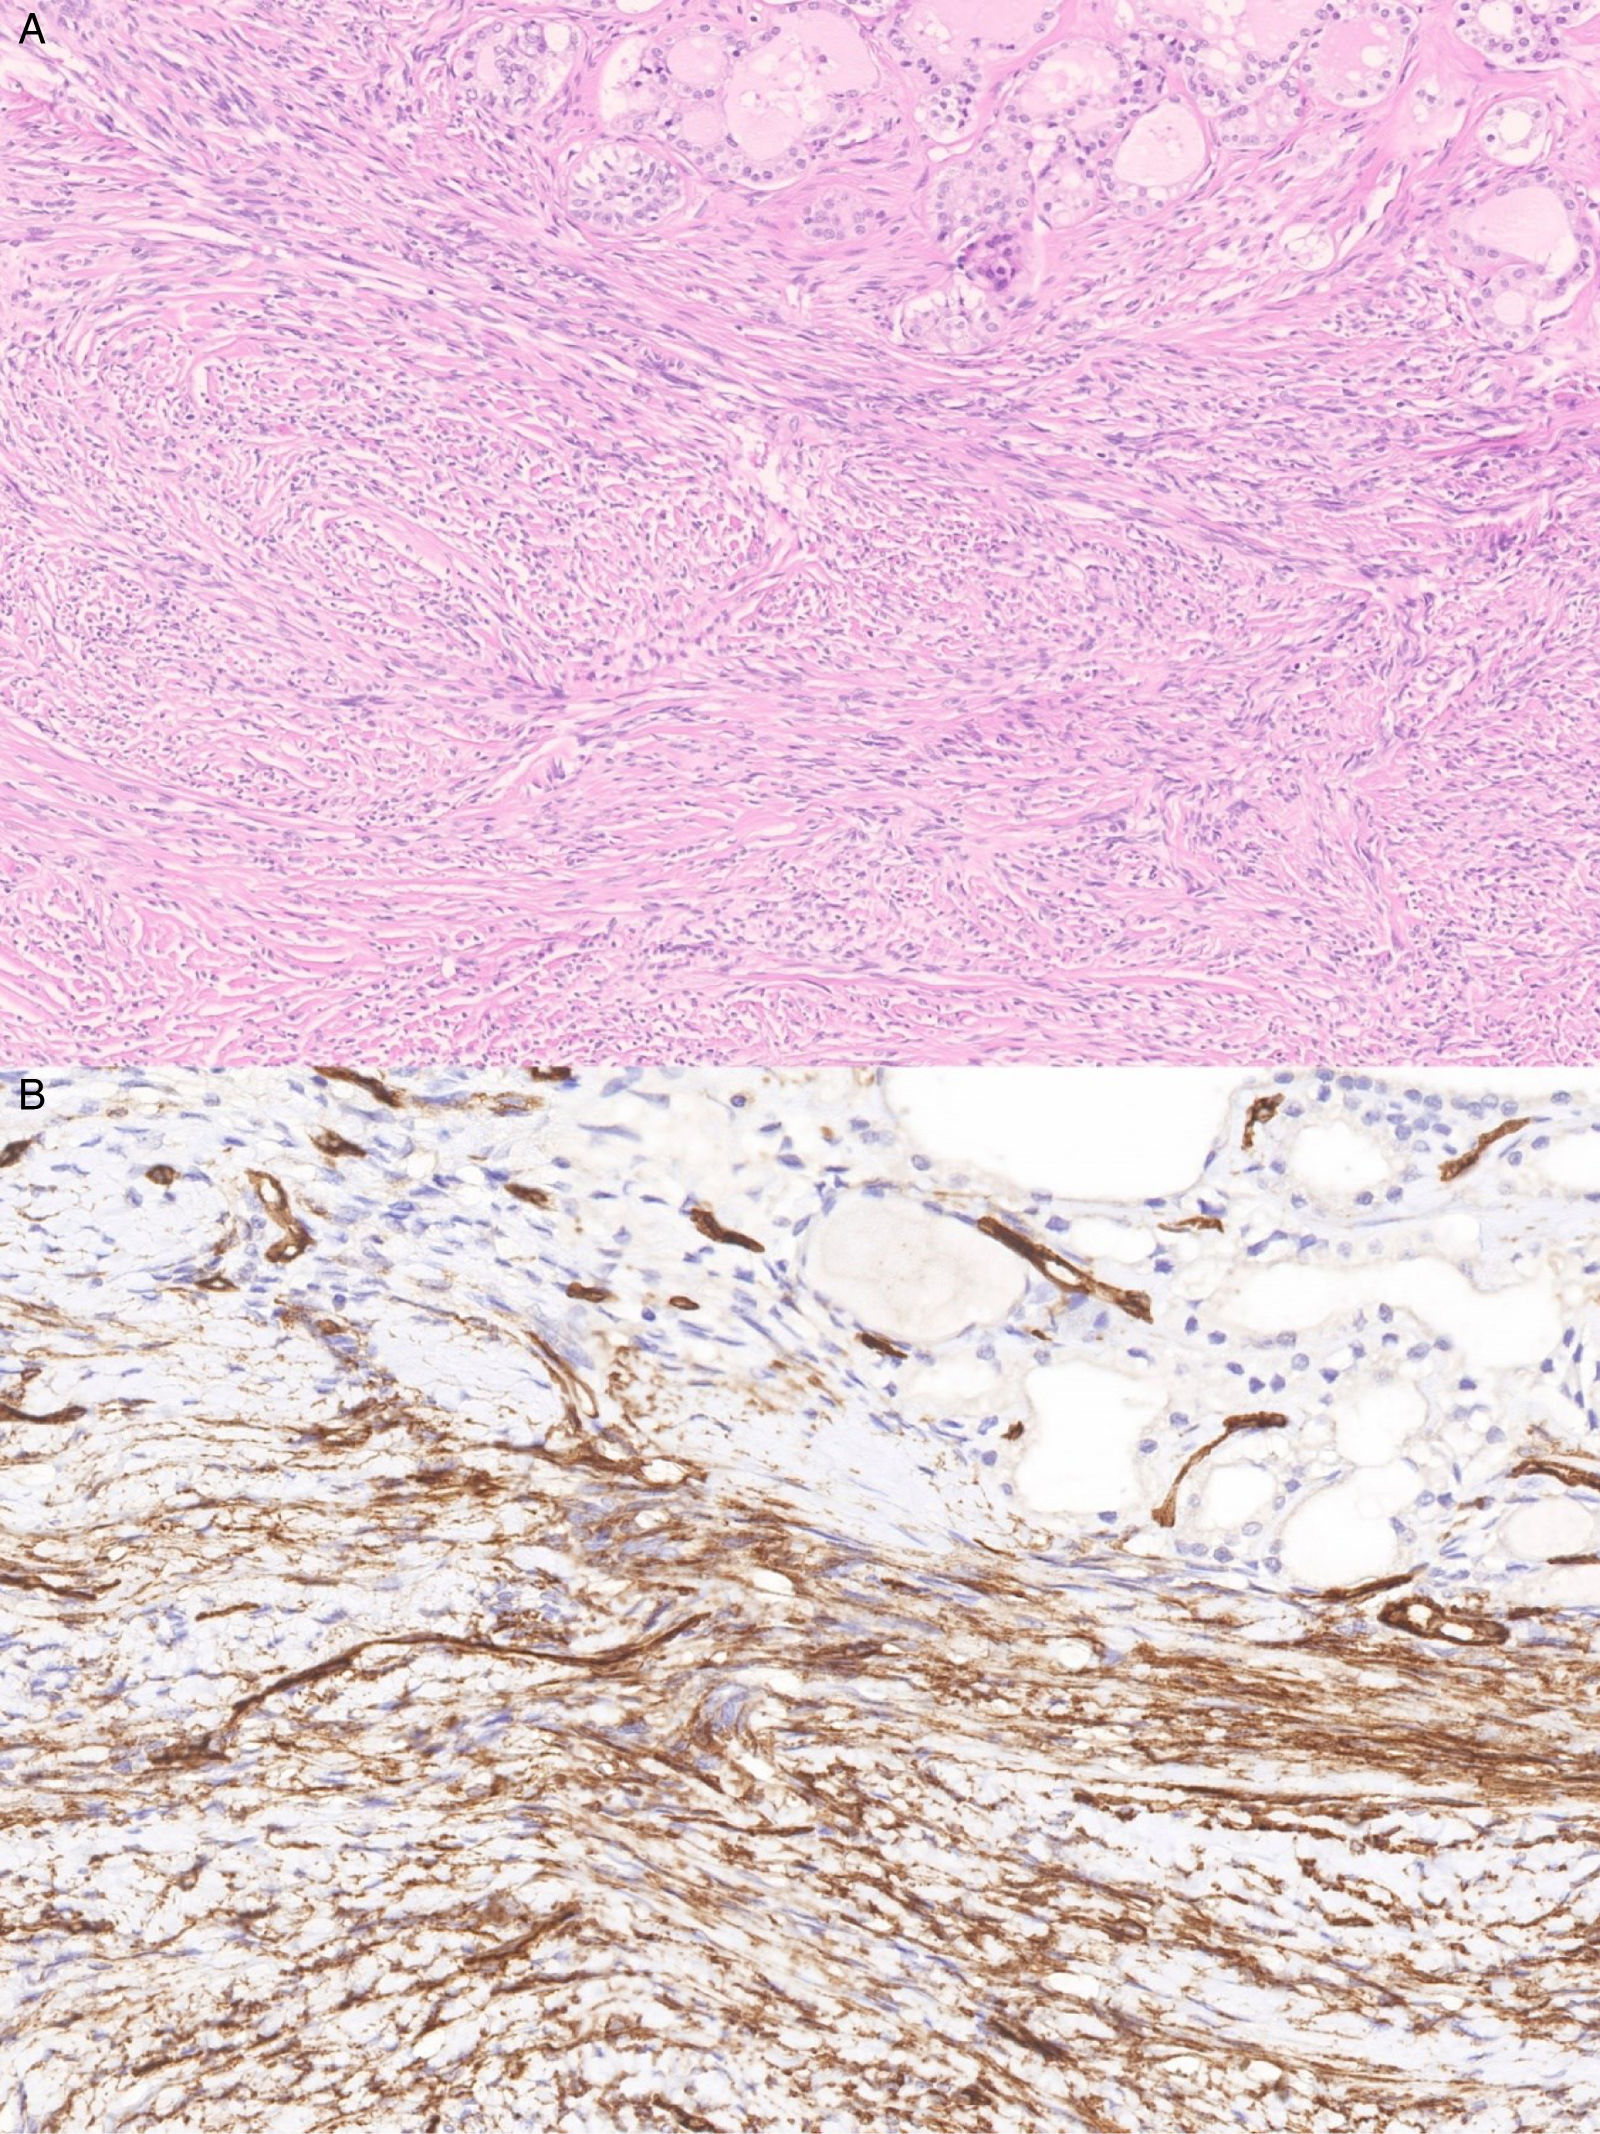

Solitary fibrous tumor (SFT) is a type of fibroblastic neoplasm with characteristic histological features, typically showing cytoplasmic expression of CD34 and nuclear expression of STAT6, associated with NAB2-STAT6 gene fusion. Thyroid localization is exceptionally rare, with only 51 cases reported worldwide to date. Its behavior in the thyroid is generally benign, although it may exhibit rapid growth, and its treatment is primarily surgical. The NAB2-STAT6 gene fusion, detected by immunohistochemistry, is pathognomonic for SFT. As exemplified in the present case, core needle biopsy (CNB) is more likely to provide sufficient material for microscopic, immunohistochemical, and other diagnostic techniques.